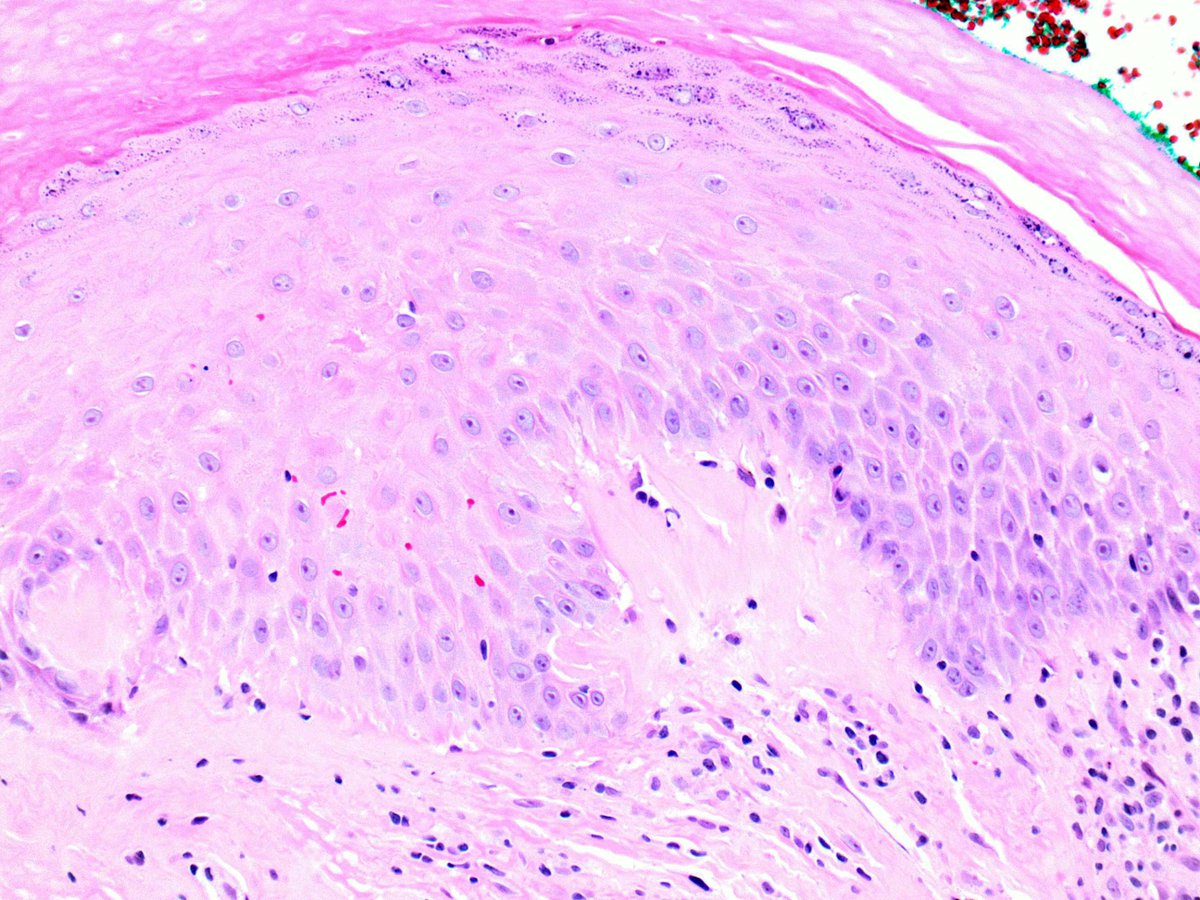

It seems like a banal SCC with keratoacanthomatous features, but it is a drug reaction pattern to treatment for metastatic melanoma with BRAF inhibitor. Take care

#dermatology#oncology#dermpath#dermatopathology#patologia#patología#pathologypic.twitter.com/ayrciZL6cL